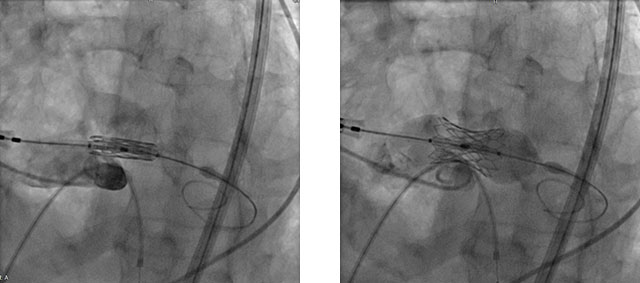

术中,送入球囊扩瓣膜系统,完成瓣膜对位,随后边调弯,边推送,顺利过弓。精准定位后,以180次/分快速起搏,并保证1:1完全夺获,使收缩压降到50 mmHg以下,迅速释放瓣膜。术后复查造影结果显示,无残余瓣周漏,猪尾导管测压显示术后主动脉瓣即刻跨瓣压差几乎为零,顺利结束手术。

球囊预扩张 瓣膜跨弓

成功跨瓣,精确定位 瓣膜释放

此例患者为96岁高龄的老年患者,也是我院开展TAVR治疗年龄最大的患者。由于患者年龄较高,因此血管入路十分迂曲,解剖结构异常复杂,从升主动脉开始,一直到主动脉弓,降主动脉,胸、腹主动脉严重迂曲;升主动脉扩张,主动脉根部成角达到69°,为严重横位心。考虑到患者复杂的解剖结构,和不太理想的血管入路,手术团队选择了新型瓣膜系统。手术过程中,考虑到患者瓣膜钙化严重,结合本中心丰富的临床经验,特选择小球囊在主动脉瓣开口进行预扩张,目的是在扩张主动脉瓣开口,为后续跨瓣操作提供良好通路。同时,避免因预扩操作导致主动脉瓣返流,造成血流动力学不稳定。在瓣膜过弓和跨瓣的操作中,瓣膜的释放位点一定要找准共平面,选择在稍高的位置进行释放,瓣膜支架膨胀后十分牢固,即刻血流状态也十分令人满意。